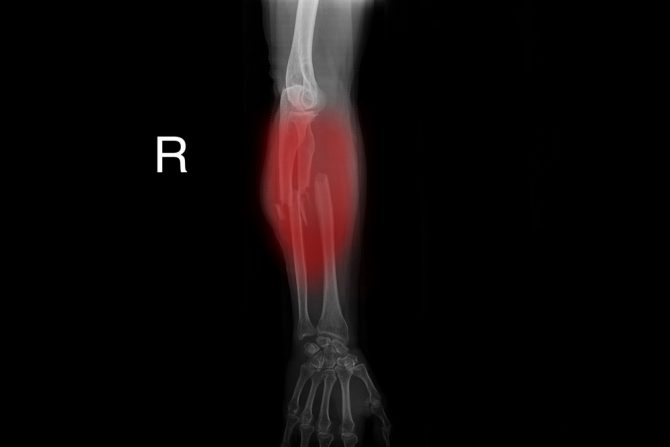

Prelom zgloba - Slomljeni zglob (fraktura zgloba) može zahvatiti male kosti u zglobu ili krajeve kostiju podlaktice. Prelomi ručnog zgloba najčešće nastaju kada ljudi pokušavaju da se uhvate tokom pada i padnu na ispruženu ruku. Lečenje može podrazumevati udlagu, gips ili operaciju, u zavisnosti od težine i količine pomeranja preloma. Hirurgija često uključuje upotrebu igala ili ploča i šrafova kako bi se slomljene kosti držale u odgovarajućem položaju dok zarastaju. Rehabilitacija je važan deo procesa lečenja, sa primarnim ciljevima vraćanje opsega pokreta, snage i funkcije.